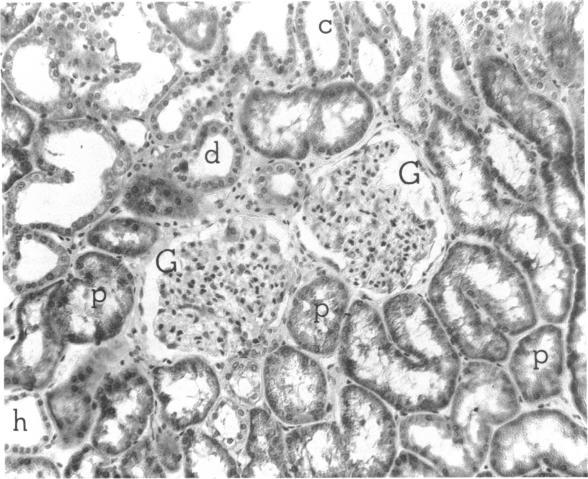

Most human pyelonephritis Escherichia coli isolates express both mannose (MS)- and globoside (Gal-Gal)-binding pili. An ascending E. coli urinary tract infection model was established in the 16-wk-old female BALB/c mouse to compare the pathogenic significance of MS and Gal-Gal pili and their efficacy as vaccines for the prevention of pyelonephritis. The distribution and density of pilus receptor compounds in urogenital tissues and as soluble compounds in urine were determined with antibodies to the synthetic receptor analogues, alpha D-Gal(1----4) beta D-Gal and alpha D-Man(1----2) alpha D-Man. Both carbohydrates were detected in vagina, bladder, ureter, and renal pelvis epithelium and in collecting duct and tubular cells. A pilus receptor compound also was detected in urine. It competitively inhibited the binding capacity of MS pili and was found to be physically, chemically, and immunologically related to Tamm-Horsfall uromucoid. Infectivity and invasiveness were quantitatively and histologically characterized for four E. coli strains: J96, a human pyelonephritis strain that expresses both MS and Gal-Gal pili; two recombinant strains prepared from J96 chromosomal DNA encoding MS pili or Gal-Gal pili; and the nonpiliated K12 recipient. Intravesicular administration of J96 (10(6) colony-forming units [CFU]) resulted in renal colonization and invasion in each of nine mice. The Gal-Gal clone (10(6) CFU) colonized the kidneys in each of 10 mice but did not invade. In contrast, the MS clone (10(6) CFU) did not colonize renal epithelium or invade. This effect was superceded when larger doses (greater than or equal to 10(10) CFU) of the MS clone were administered in volumes that cause acute vesicoureteric reflux. The efficacy was determined of vaccines composed of pure MS or Gal-Gal pili or the lipopolysaccharide containing O somatic antigen of the challenge strain, J96. The Gal-Gal pilus vaccine blocked renal colonization in 19 of 22 mice and renal invasion in 10 of 11 mice. Gal-Gal pili may be useful immunogens for the prevention of pyelonephritis in anatomically normal urinary tracts.

大多数人类肾盂肾炎大肠杆菌分离株都表达甘露糖(MS)结合菌毛和糖苷(Gal-Gal)结合菌毛。在16周龄雌性BALB/c小鼠中建立了大肠杆菌上行性尿路感染模型,以比较MS菌毛和Gal-Gal菌毛的致病意义及其作为预防肾盂肾炎疫苗的效果。用针对合成受体类似物α-D-Gal(1→4)β-D-Gal和α-D-Man(1→2)α-D-Man的抗体,测定泌尿生殖组织中菌毛受体化合物的分布和密度以及尿液中可溶性化合物的情况。在阴道、膀胱、输尿管、肾盂上皮以及集合管和肾小管细胞中均检测到这两种碳水化合物。在尿液中也检测到一种菌毛受体化合物。它能竞争性抑制MS菌毛的结合能力,并且在物理、化学和免疫学上与Tamm-Horsfall尿黏蛋白相关。对四株大肠杆菌进行了感染性和侵袭性的定量及组织学特征分析:J96,一株表达MS菌毛和Gal-Gal菌毛的人类肾盂肾炎菌株;由编码MS菌毛或Gal-Gal菌毛的J96染色体DNA制备的两株重组菌株;以及非菌毛化的K12受体菌。膀胱内接种J96(10⁶菌落形成单位[CFU])导致9只小鼠中的每只都出现肾脏定植和侵袭。Gal-Gal克隆株(10⁶CFU)使10只小鼠中的每只都出现肾脏定植,但未发生侵袭。相比之下,MS克隆株(10⁶CFU)未在肾上皮定植或侵袭。当以导致急性膀胱输尿管反流的体积给予更大剂量(大于或等于10¹⁰CFU)的MS克隆株时,这种效应被取代。测定了由纯MS菌毛或Gal-Gal菌毛或含有攻击菌株J96的O菌体抗原的脂多糖组成的疫苗的效果。Gal-Gal菌毛疫苗在22只小鼠中的19只中阻止了肾脏定植,在11只小鼠中的10只中阻止了肾脏侵袭。Gal-Gal菌毛可能是预防解剖结构正常的尿路肾盂肾炎的有用免疫原。